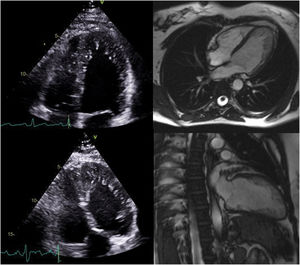

The family pedigree (Figure 2) revealed that both the patient's parents were already deceased, the father from dementia and the mother from cancer. The patient had nine siblings, including one sister who died in childhood of unknown cardiac disease and one brother who died in infancy of unknown cause. Two other brothers were deceased, one from pneumonia in infancy and one from cancer at 27 years of age. Her 49-year-old brother underwent transthoracic echocardiography, which was normal. Her 47- and 41-year-old sisters also underwent echocardiographic screening (Figure 3) and both exams resulted in a diagnosis of LVNC (Table 2). They also underwent MRI which corroborated these findings (Figure 3). The 41-year-old sister has an eight-year-old son who was also diagnosed with LVNC by echocardiographic screening. Her 28-year-old daughter has a normal echocardiogram and her 22-year-old son had pronounced LVNC with right ventricular involvement on the echocardiogram as well as on cardiac MRI (Figure 4). He also received an ICD due to non-sustained VT.

| Sister, 47 years | Effort dyspneaPalpitations | Normal LV functionHypertrabeculated myocardium meeting the Chin, Jenni and Stöllberger criteria of LVNC | Petersen criteria of LVNC (ratio of thickness of noncompacted/compacted layers: 3.5)LVEF: 59%No late enhancement |

| Sister, 41 years | Asymptomatic | Normal LV functionHypertrabeculated myocardium meeting the Chin, Jenni and Stöllberger criteria of LVNC | Petersen criteria of LVNC (ratio of thickness of noncompacted/compacted layers: 2.8)LVEF: 64%No late enhancement |